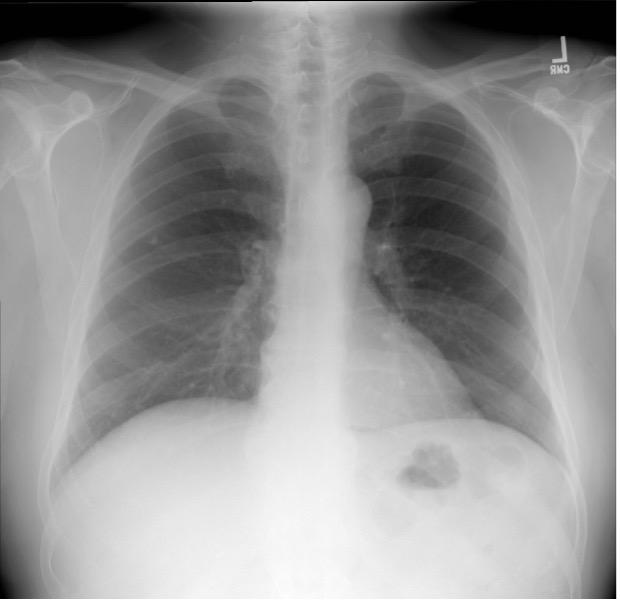

A 61-year-old woman with mild persistent asthma controlled with inhaled corticosteroids and an as needed albuterol inhaler presents to the emergency department with shortness of breath and audible “wheezing” for approximately 5-7 days after a total thyroidectomy for papillary carcinoma of the thyroid. The difficulty with breathing has steadily worsened, despite increasing use of albuterol. She reports a tingling sensation around the mouth and numbness in her hands and feet with sporadic muscle cramps mainly in the legs throughout the day and especially at night. On physical examination, she appears to be in mild respiratory distress, with a respiratory rate of 22 breaths/min, using some accessory muscles, and not being able to finish all her sentences. Lung examination is significant for expiratory wheezing throughout all fields. A chest radiograph is performed (see figure below). An arterial blood gas is drawn and shows a pH of 7.36, PCO2 of 40 mm Hg, and PO2 of 90 mm Hg on 2 L nasal cannula oxygen. The patient is given intravenous glucocorticoids and continuously nebulized albuterol and ipratropium. Despite this, she remains symptomatic with audible stridor.